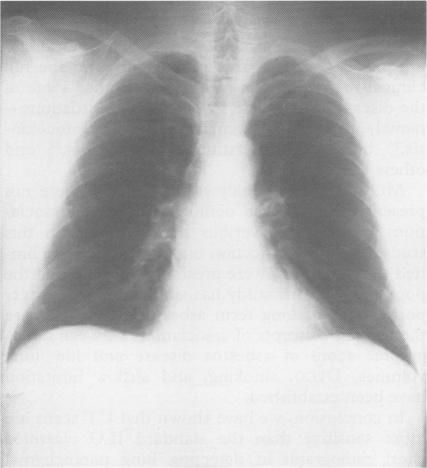

Computed tomography (CT; both conventional (CCT) and high resolution (HRCT)) scans of the thorax were evaluated to detect early asbestosis in 61 subjects exposed to asbestos dust in Québec for an average of 22(3) years and in five controls. The study was limited to consecutive cases with chest radiographs of the International Labour Organisation categories 0 or 1 determined independently. All subjects had a standard high kilovoltage posteroanterior and lateral chest radiograph, a set of 10-15 1 cm collimation CCT scans and a set of three to five 2 mm collimation HRCT scans in the upper, middle, and lower lung fields. Five experienced readers independently read each chest radiograph and sets of CT scans. On the basis of three to five readers agreeing for small opacities of the lung parenchyma, 12/46 (26%) negative chest radiographs were positive on CT scans, but 6/18 (33%) positive chest radiographs were negative on CT scan. On the basis of four to five readers agreeing on a chest radiograph, 36/66 (54%) subjects were normal (group A), 17/66 (26%) were indeterminate (group B), and 13/66 (20%) were abnormal (group C). By the combined readings of CCT and HRCT, 4/31 (13%) asbestos exposed subjects of group A were abnormal (p < 0.001), 6/17 (35%) of group B were abnormal, and in group C, 1/13 (8%) was normal, 2/13 were indeterminate, and 10/13 (77%) were abnormal. Separate readings of CCT and HRCT on distinct films in 14 subjects showed that all cases of asbestosis were abnormal on both CCT and HRCT. Inter-reader analyses by kappa statistics showed significantly better agreement for the readings of CT than the chest radiographs (p < 0.001), and for the reading of CCT than HRCT (p < 0.01). Thus CT scans of the thorax identifies significantly more irregular opacities consistent with the diagnosis of asbestosis than the chest radiograph (20 cases on CT scans v 13 on chest radiographs when four to five readers agreed, 13% of asbestos exposed subjects with normal chest radiographs or 21% of asbestos exposed subjects with normal or near normal chest radiographs. It decreased the number of indeterminate cases significantly from 17 on chest radiographs to 13 on CT scans. All cases of asbestosis detected only on CT scans were similarly seen on CCT and HRCT and did not have significant changes in lung function. The CT scans significantly reduced the inter-reader variability, despite the absence of ILO type reference films for these scans.